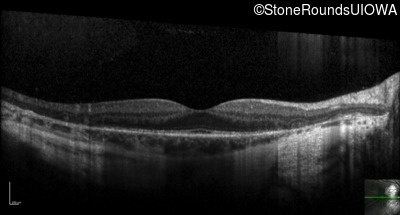

Optical Coherence Tomography - Right - 20/16

Exemplar / OCT Stack

OCT Stack